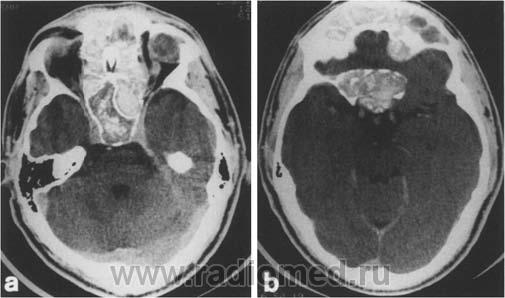

Наблюдение на самом деле весьма редкое и интересное. Для начала; это не эхинококк и конечно не мезотелиома. Данные заболевания не дают такую скиалогическую КТ картину: полость с содержимым, серпом воздухом и с деструкцией рёбер, лопатки и инвазией грудной стенки. Такой агрессивный характер инфекции может быт при актиномикозе; но при нём идёт диффузный процесс; не характерно образование таких больших полостей с внутренними включениями.

Аспергиллус может расти инвазивно и вызывать деструкцию в костях; есть отдельная форма: инвазивный аспергиллёз... Я прикрепил ниже сканы аспергиллёза с инвазией основания черепа. Но для неё не характерно образование полостей с "грибковым шаром"... Это признак мицетемы (отдельная форма аспергиллёза). Если поразмыслить логически; должен быть субстрат; а потом уже "сел" гриб. Я думаю дело было так; у пациента есть в наличии мелкоклеточный рак лёгкого или туберкулёзная полость; а потом присоединился аспергиллус и мы получили представленную картину. По другому никак не укладывается. ИМХО.